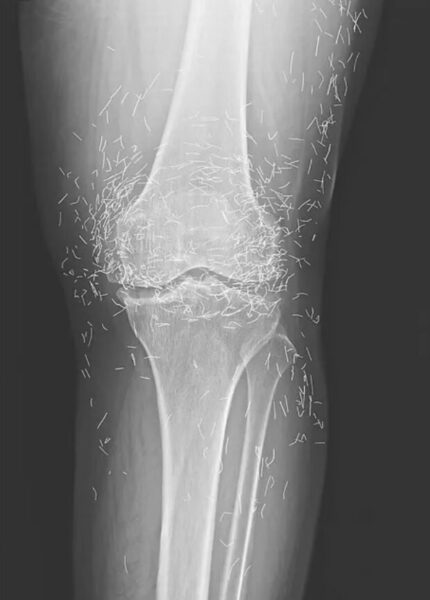

The X-rays taken at the hospital showed classic signs of osteoarthritis — but they also revealed dozens, if not hundreds, of bright flecks scattered around both knee joints. To the eye, it looked almost like a “gold mine” hidden inside her legs.

The South Korean woman’s X-rays quickly attracted attention online because they look almost unreal — as if someone had sprinkled gold dust around her bones.

Her knees appeared to be packed with tiny, shimmering pieces of gold.